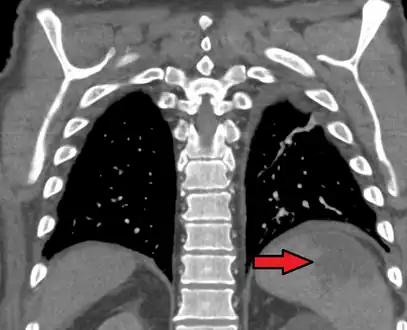

a, b) Splenic infarction.

Splenic infarct seen on CT

Although it can occur asymptomatically, the typical symptom is severe pain in the left upper quadrant of the abdomen, sometimes radiating to the left shoulder. Fever and chills develop in some cases.[3] It has to be differentiated from other causes of acute abdomen.

An abdominal CT scan is the most commonly used modality to confirm the diagnosis,[3] although abdominal ultrasound can also contribute.[16][17][18]